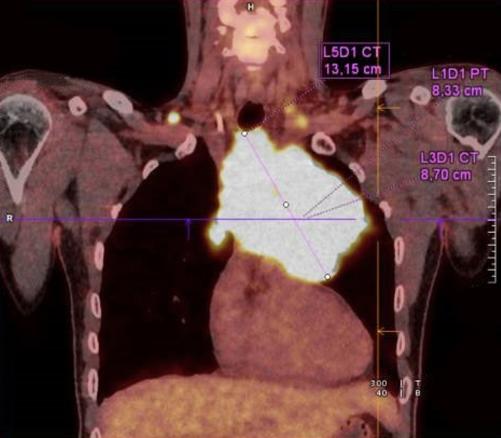

Lymphome à grandes cellules siégeant dans le médiastin antérieur. La lésion est le plus souvent volumineuse, elle peut envahir les organes de voisinage et entrainer un syndrome cave supérieur.